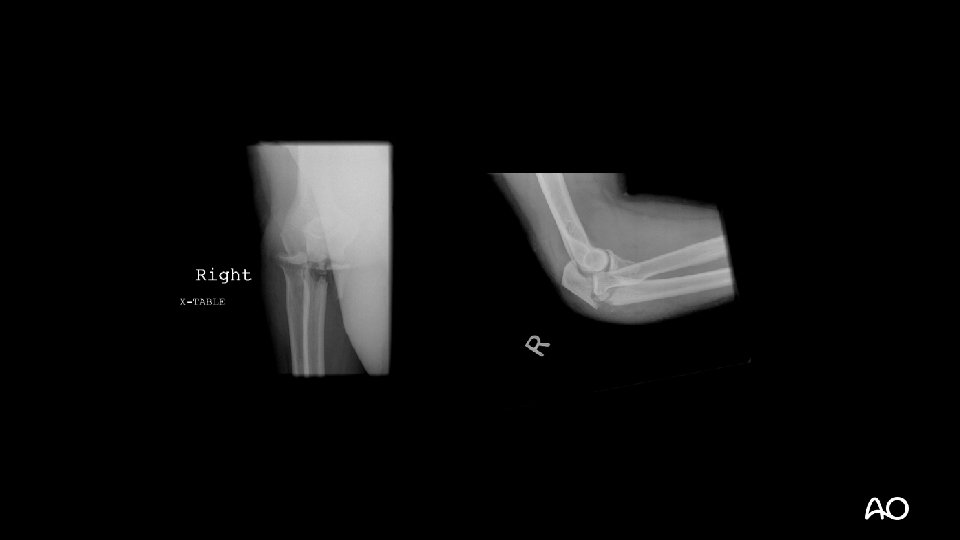

Case 1

Terrible triad fracture dislocation • Historically poor outcomes • Injury “triad”: • Elbow dislocation (often posterior) • Radial head fracture • Coronoid fracture